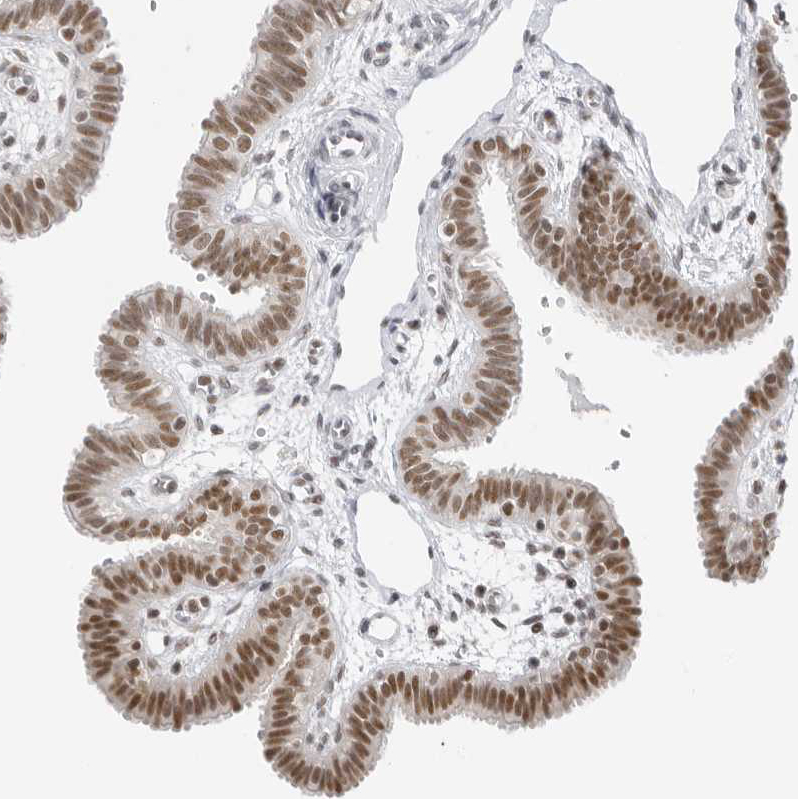

Immunohistochemical staining of human Testis cancer, carcinoma shows strong nuclear positivity in tumor cells.